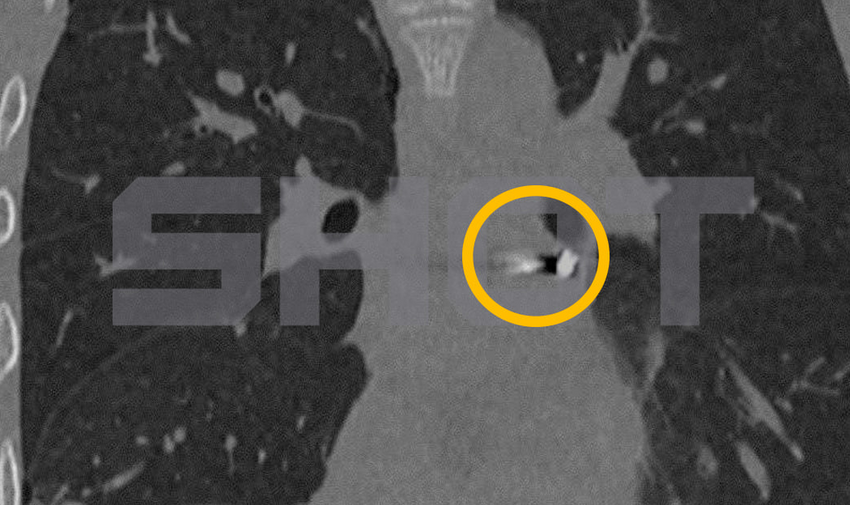

Парня с пулевым ранением доставили на скорой в Детский центр имени Рошаля. Он вместе с приятелями захотел пострелять из пневматического оружия. В итоге пулю получил сам мальчик. Инородное тело застряло в миллиметрах от жизненно важных структур в наружной оболочке сердца.

Врачи провели экстренную операцию, в ходе которой удалось извлечь пулю с помощью специальных инструментов и без единого разреза. Мальчик в стабильном состоянии и скоро будет полностью здоров.